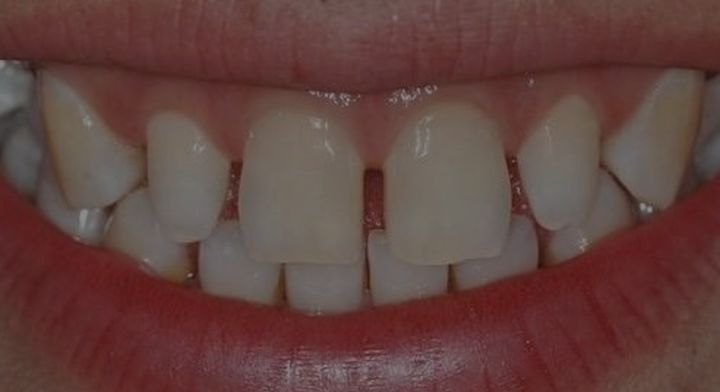

美容牙冠的存在,是因为有需求的存在,并不是所有牙齿不齐的人都有时间或者金钱去做牙齿矫正。例如很多前牙散在间隙的成年人,接受不了几万块的牙齿矫正方案,只舍得去小诊所花几千块做金属烤瓷冠关闭牙缝。

你说他们不知道牙齿矫正的方案更好?他们不知道金属烤瓷冠的弊病?大部分做全冠的人是知道的,但为什么还要退而求其次?那是因为没钱!